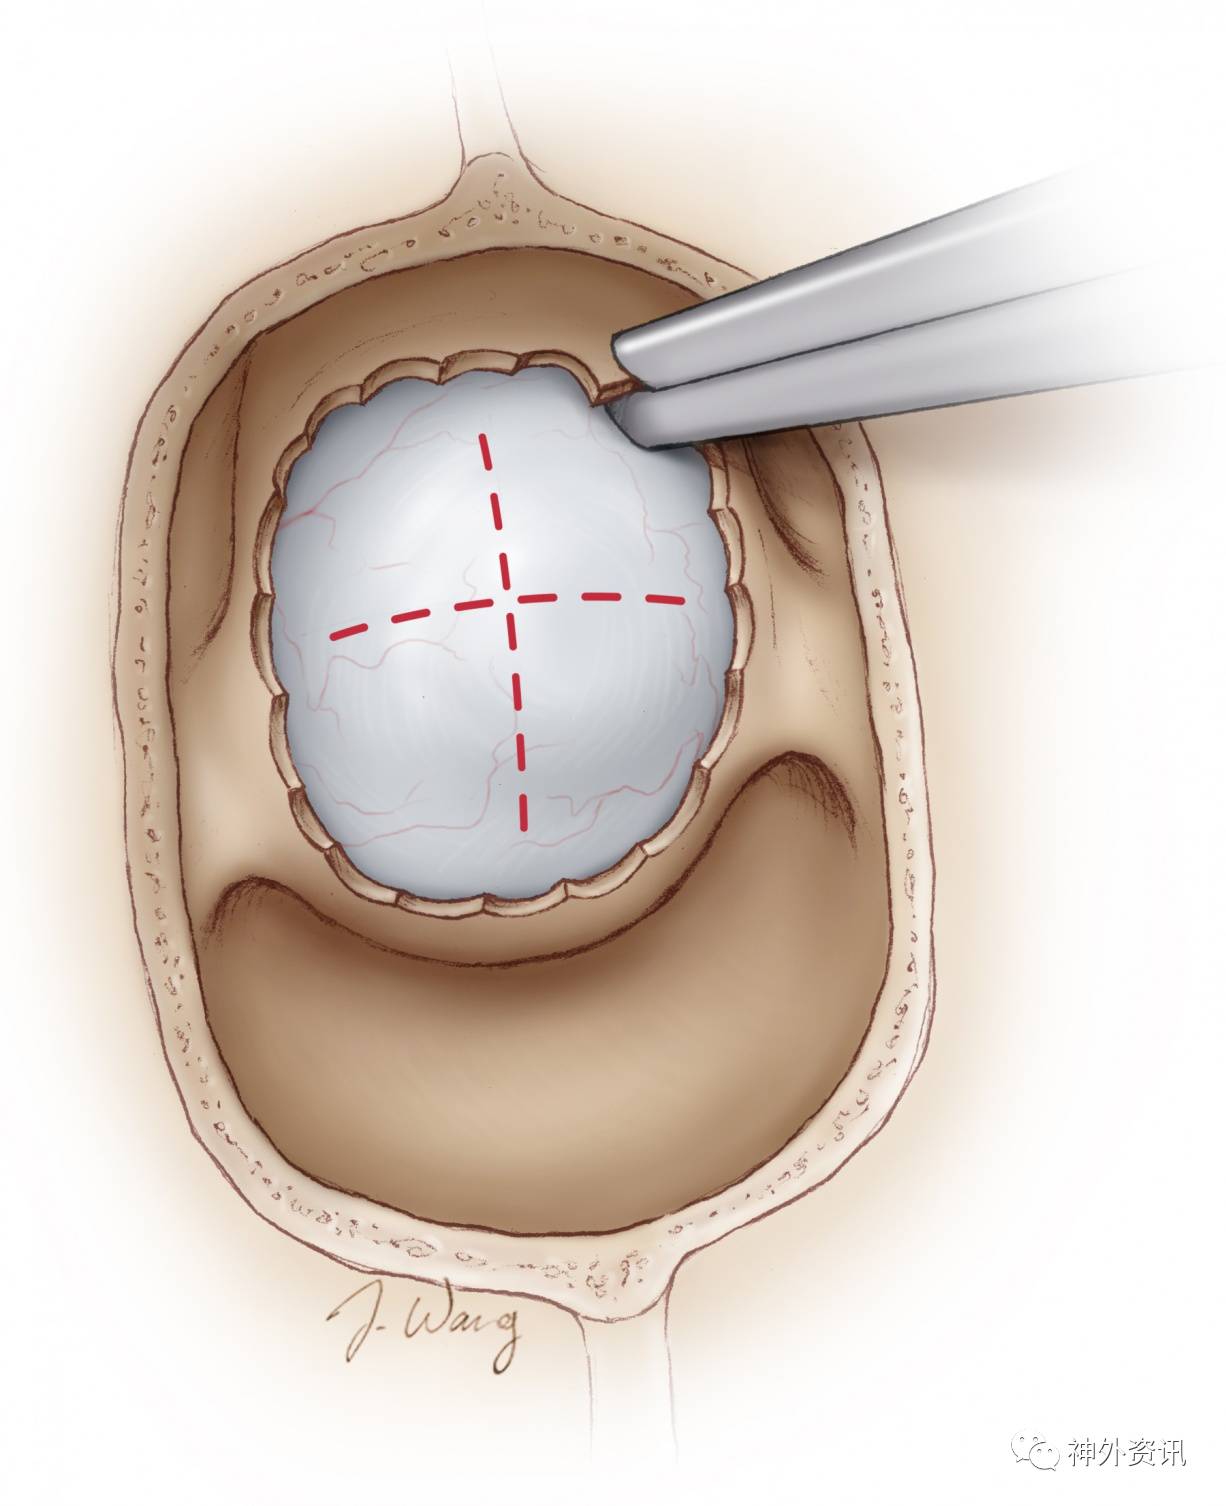

图19. 进一步扩大骨窗主要为了最大限度切除肿瘤。实际上,笔者相信经蝶入路肿瘤仅实现次全切除的最重要原因,是没有形成最佳的鞍底骨窗,特别是侧方的骨窗。骨窗的开放应外延至双侧颈动脉水平,前方至鞍结节。

图中红虚线示硬脑膜“十”字切口,适用于切除鞍内及鞍上病变。不充分的硬膜开口可能使肿瘤切除困难,并且可能因为术者的盲点,妨碍肿瘤侧方最大程度的切除。便携的多普勒探头应该用于引导硬膜切开,如果动脉被推移到中央,硬脑膜开口应调整,否则可能损伤动脉。